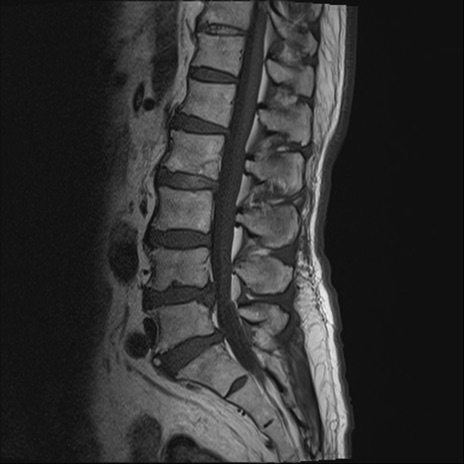

【整形】TIPS症例2 腰椎MRI T1WI(矢状断像)

【症例】70歳代男性

【主訴】左下肢痛

【現病歴】2週間前くらいから腰痛、左下肢痛あり。左臀部から大腿、下腿外側のしびれが常時ある。歩行とともに同部位の痛みあり。

【身体所見】Lasegue70-/60+、Bragard-/±、PTR ±/±、ATR -/-、IP 5/5、TA 5/4、TS 5/5、EHL 右第1足趾なし/3、FHL 5/5、hypersthesia(-)、足背動脈触知良好

異常所見と診断は?